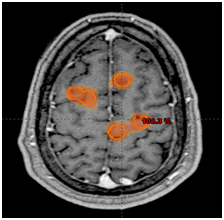

A 63-year-old woman with a history of breast cancer of 5years of evolution with bones metastasis controlled with systemic treatment and 2years later presented cerebral metastases treated with WBRT sparing both hippocampus (20Gy in 5 fractions). One year at the end she has new brain progression without neurological symptoms and controlled systemic disease. We evaluated the case and in view of the good general condition we indicated re-irradiation with radiosurgery to all visible lesions: 83 (eighty-three) in total (Figure 1). The total volume of disease was 34cc and the dose prescription of SRS 27Gy in 3 fractions. For the treatment, we used a dedicated linear accelerator (LINAC) Trilogy Varian, frame less immobilization and RapidArc modulated intensity radiotherapy technique (IMRT) with an treatment isocenter. After 6months of follow-up, there was no neurocognitive impairment or alteration of quality of life, without systemic progression and in the brain resonance complete response was seen in 90% of the lesions with tumor control of all the metastases (Figure 2).

Figure 2 RapidArc IMRT technique.